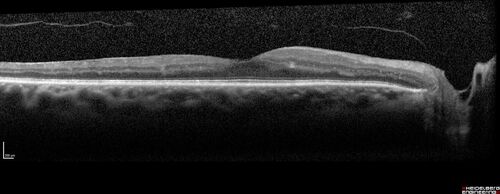

Prethreshold PDR right eye - mild NVD

Pre-Threhold PDR right eye NVD